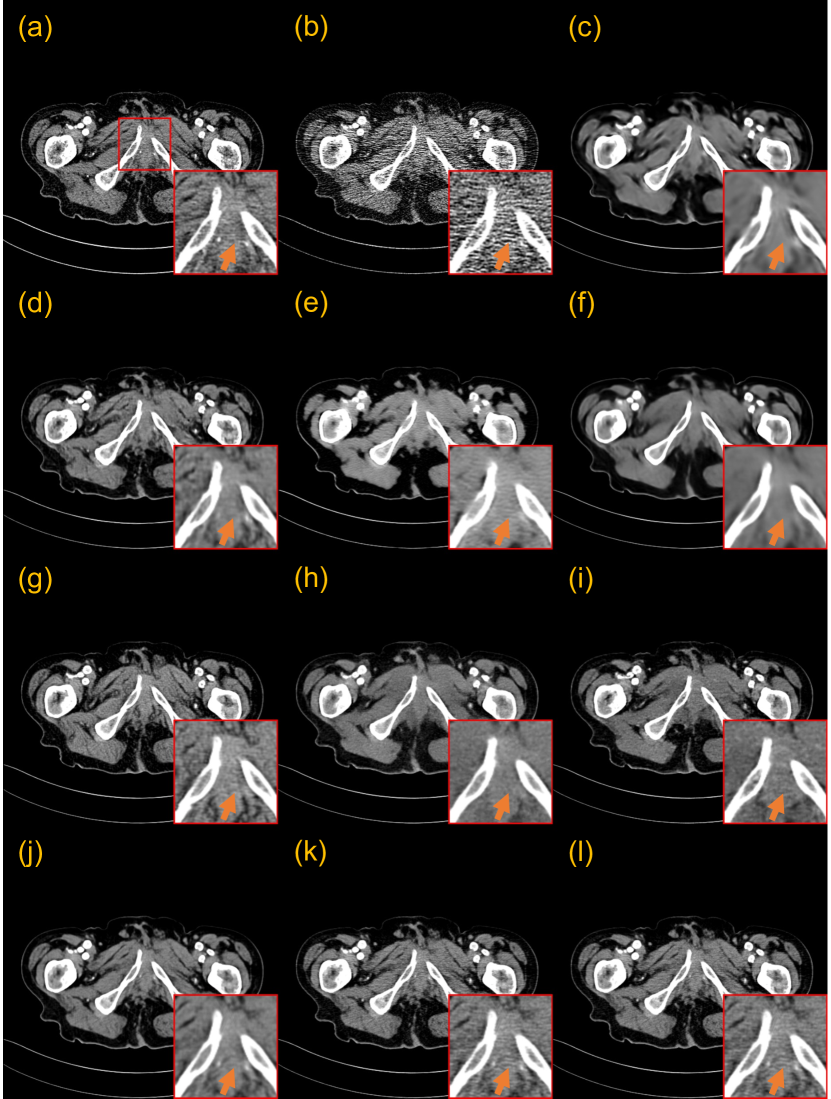

3.5.3 Generalization to the piglet dataset

We also examined the proposed one-shot framework in enhancing the generalization performance on the piglet dataset. We tested all the trained models on 25% and 10% doses of data from the piglet dataset. One slice is also selected from this piglet dataset with its (un)paired normal-dose slice to train our CoreDiff+OSLp, and CoreDiff+OSLu.

Figs. 12 and 13 show the denoising results of two representative slices of 25% and 10% doses. In the 10% dose scenario, RED-CNN, WGAN-VGG, and CNCL-U-Net severely blur the denoised image. While DU-GAN and IDDPM manage to avoid global smoothing, they still result in the loss of crucial local details. PDF-RED-CNN and CoreDiff successfully preserve fine details. When integrated with the OSL framework, the denoised images from CoreDiff+OSLp and CoreDiff+OSLu exhibit textures closest to the NDCT image. CoreDiff+OSLp and CoreDiff+OSLu also improve the quantitative performances over CoreDiff, and outperform other methods. In the 25% dose scenario, surprisingly, the quantitative metrics of the remaining methods except CoreDiff+OSLp and CoreDiff+OSLu are even worse than that of FBP. This observation highlights the limitations of DL-based models when generalizing across multi-center, multi-species CT data. However, the denoised images by CoreDiff+OSLp and CoreDiff+OSLu within our OSL framework consistently demonstrate superior visual quality and quantitative performance.